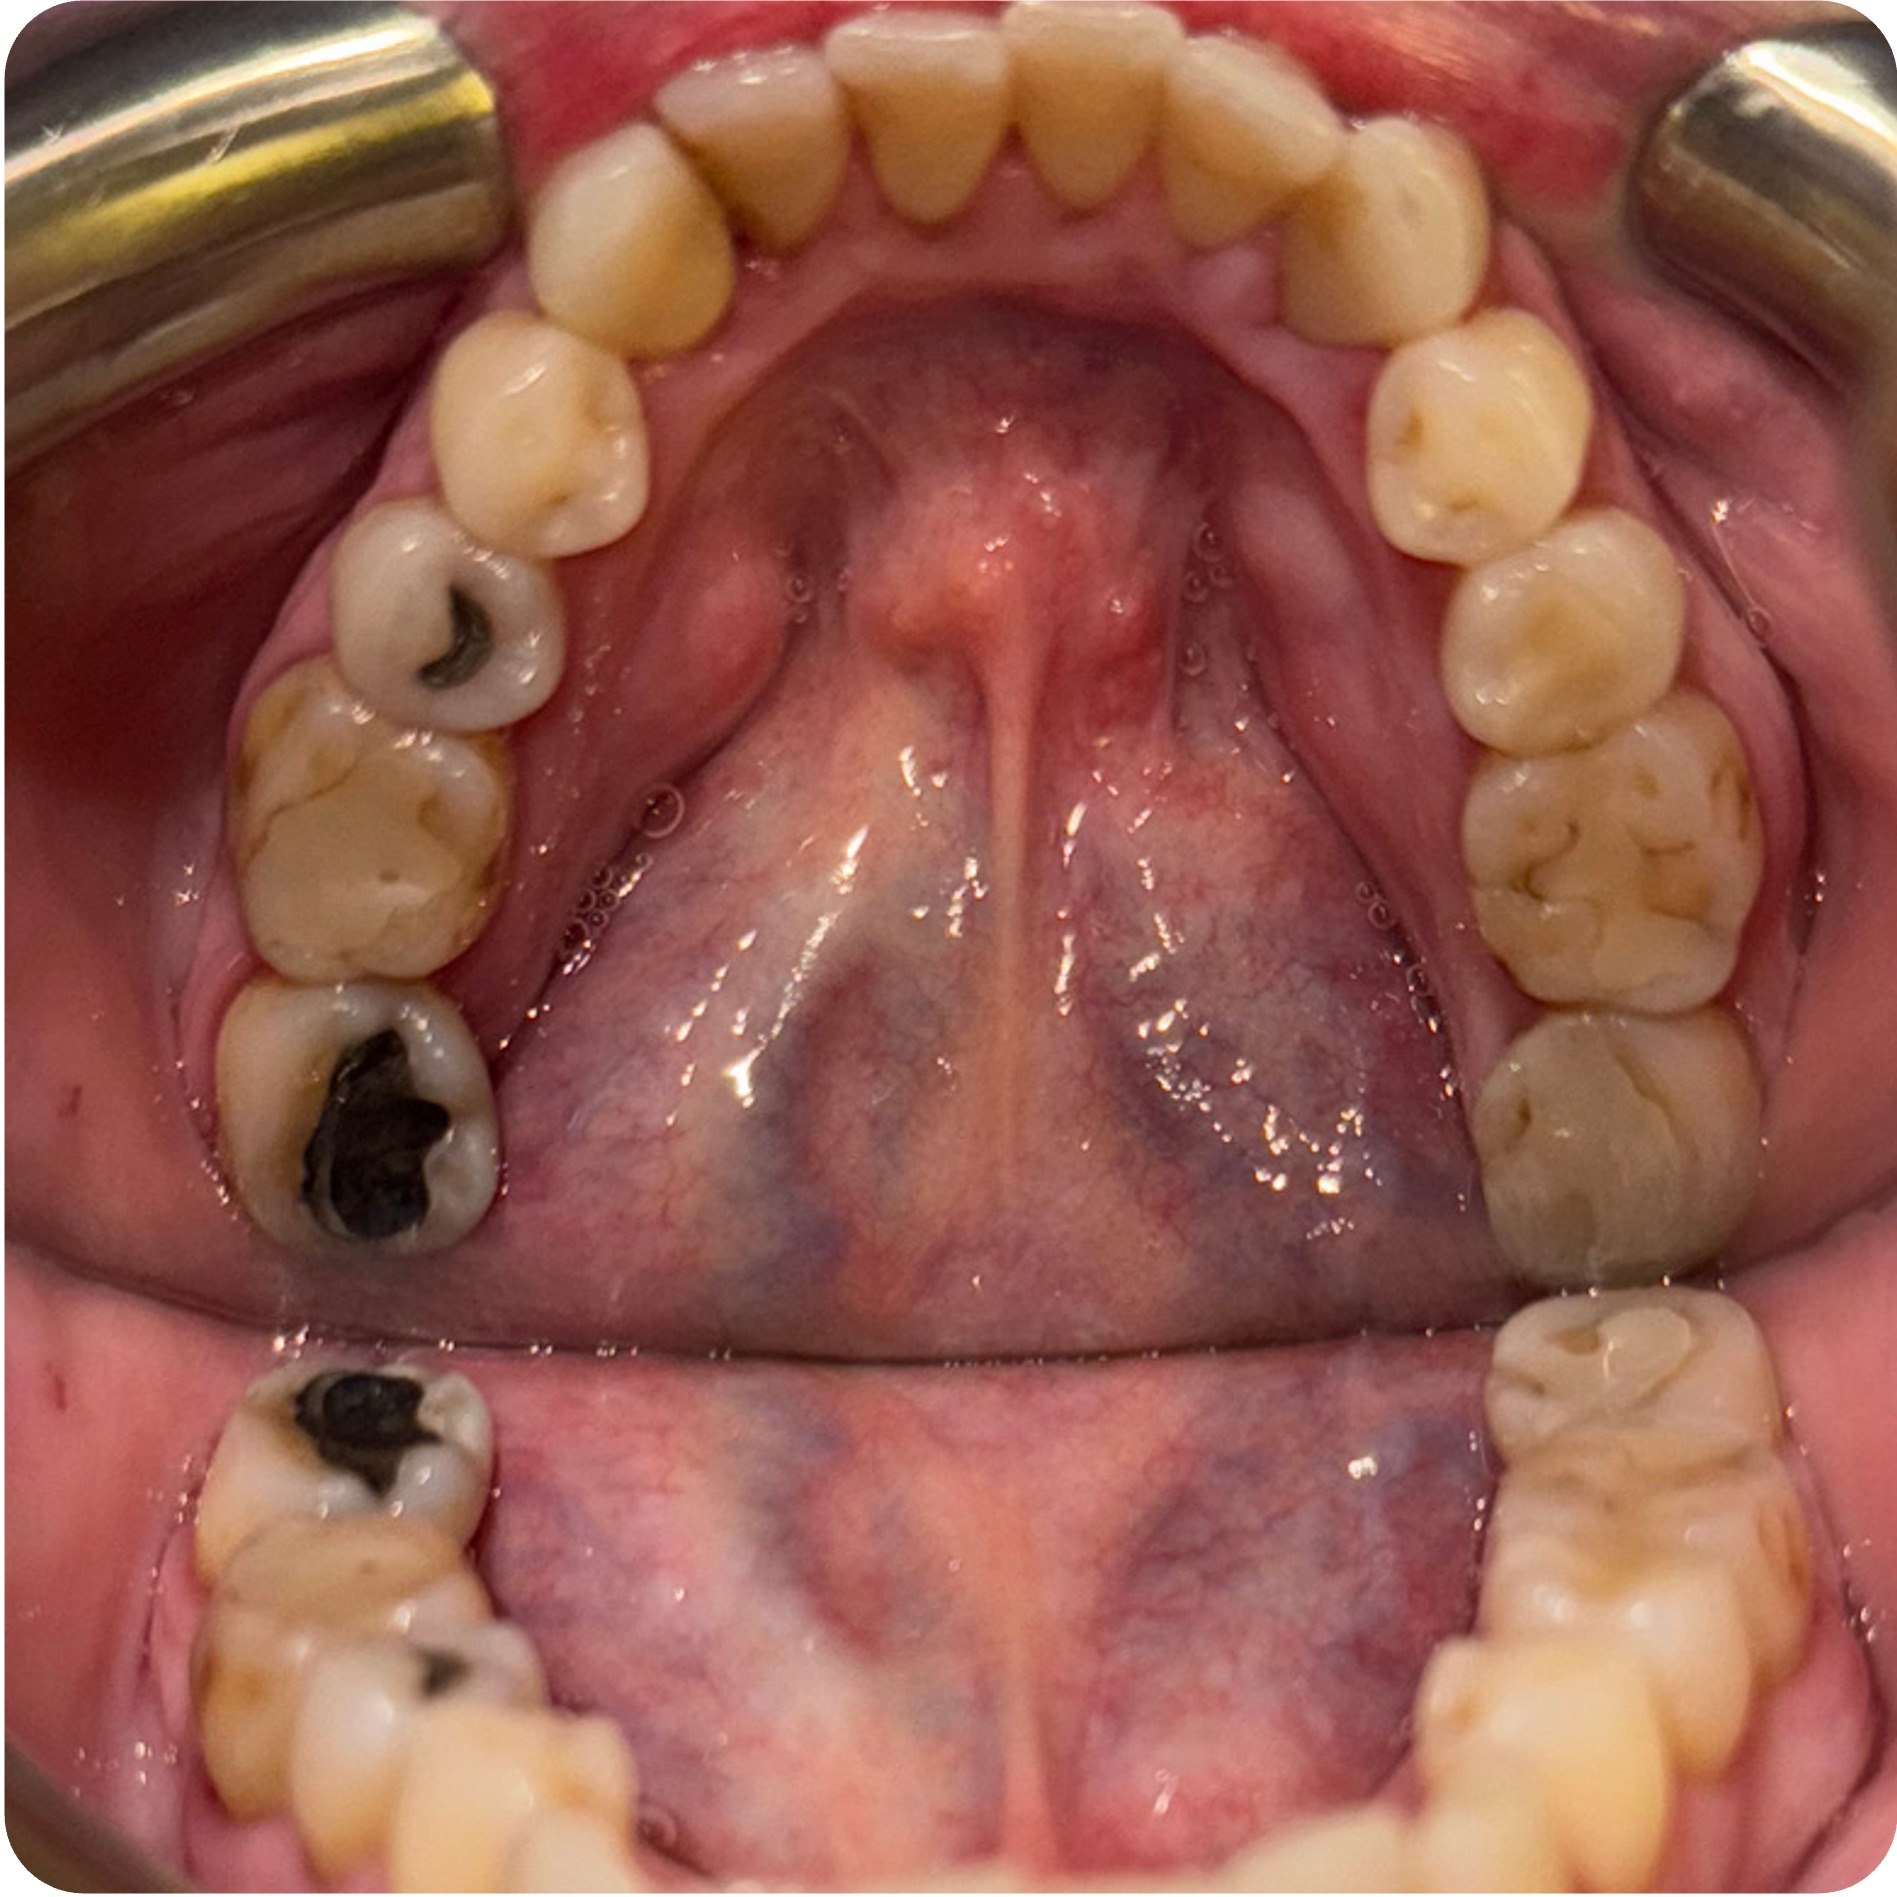

This case follows Roberta, a 65-year-old female, through a multi-stage biological dentistry process involving CBCT-based full visualization, extractions with bone grafting, Covered Socket Residuum (CSR) ~ Previously known as cavitation ~ protocols, periodontal therapy, and implant placement. The goal was long-term stability, function, and whole-body support—delivered with a clear, step-by-step plan.

Roberta presented with multiple areas of concern identified during a comprehensive exam and CBCT full visualization. The treatment plan was structured into phases to address infection, stabilize bone and gums, and rebuild function with implant-supported solutions where indicated.

The case included staged extractions with bone grafting, Covered Socket Residuum (CSR) ~ Previously known as cavitation ~ protocols in key areas, periodontal scaling and root planing across all quadrants, and implant placement in areas planned for long-term support.

Visual Case Progression

All clinical images are shown at a consistent size for easy comparison.